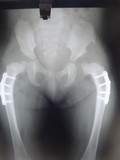

Post- operative radiograph after correction showing well reduced joint

Pre-operative radiograph of dislocation of hip joint